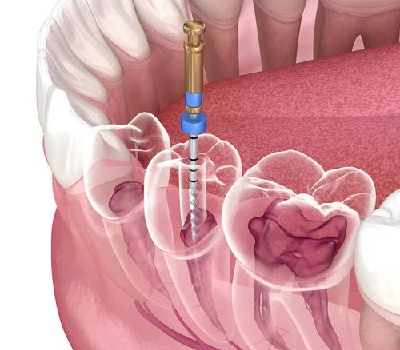

Endodontics (Root Canals)